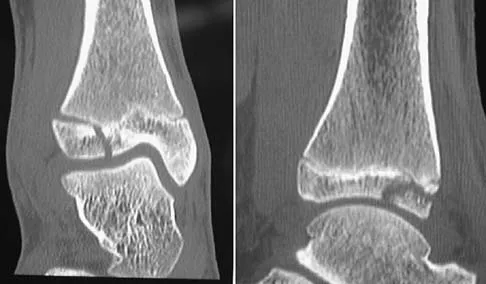

Question 57High Yield

Figures 8a through 8d show the radiographs and CT scans of a 14-year-old girl who has a painful, rigid planovalgus foot. Management consisting of arch supports and anti-inflammatory drugs failed to provide relief. A below-knee walking cast resulted in pain resolution, but she now reports that the pain has recurred. Management should now consist of

Explanation